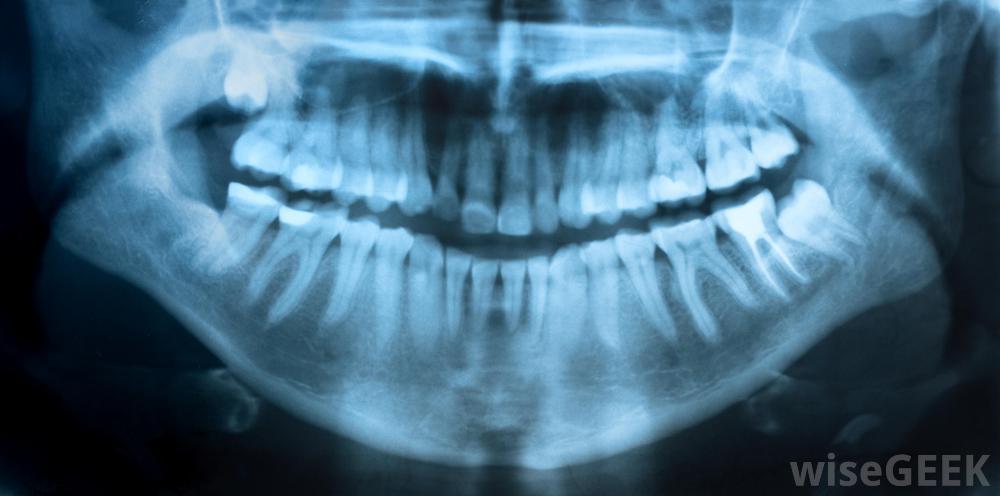

臨床牙科學涉及對牙齒和口腔其他結構進行的醫療程序的研究和實施。這些程序大多數是在牙科診所進行的,有牙醫和各種助手。該學科涵蓋了一個很大的子專業領域,包括種植牙學,牙周病學和口腔外科學。手術刀是一種用于手術的小而鋒利的刀一個典型的診所將容納一個或多個牙醫,他們可以在普通牙科工作,也可以在其中一個分支學科中擔任專家。普通牙醫對患者進行牙齒和牙齦檢查、診斷和操作。牙科助理、技術員,衛生員為牙醫提供支持。大多數員工將熟練使用各種牙科工具,如X光機、手術刀,牙科專家會強調刷牙的重要性修復受損牙齒是臨床牙科學的一個主要重點,例如,如果患者的牙齒上有洞,牙醫可能會用耐用的材料填充牙洞,或者在牙齒上覆蓋一層稱為牙冠的保護性覆蓋物另一方面,牙齒內部脆弱組織受損的個體可能需要根管切除牙齒中的神經。X光是臨床牙科的一個組成部分臨床牙科醫生也強調維護健康的牙齒。因此,許多牙科診所為病人提供清潔牙齒的服務。員工還教育病人正確的自我護理程序,如使用牙線和刷牙牙齒。如果臨床醫生發現患者的牙齒彎曲或間距過大或咬合不正,可將患者推薦給另一個臨床牙科分科醫生:正畸醫師。牙醫檢查患者;臨床牙科學的另一個共同關注點是種植體的制作和安裝。患有嚴重齲齒或損傷的患者可能需要一顆或多顆假牙。種植牙學部分類牙材料也可以作為橋梁植入患者體內。種植牙科學,包括植入人工牙來替換缺失的牙齒,是牙科臨床的一種形式牙齒并不是臨床牙科的唯一關注點。口腔內和周圍的其他支持結構,如牙齦和頜骨,也可以由牙醫研究和治療。臨床牙周病學是一門專門研究這些區域的牙科分支學科。口腔區域的幾種疾病和狀況-例如智齒拔除-也需要手術治療,這些程序是口腔或頜面部外科醫生的領域。臨床牙科認證通常需要高等教育和從認可的牙科學校畢業。額外的教育和認證可能需要專業化的必要條件。畢業后,許多牙醫選擇開私人診所,而其他人則在更大的機構中尋找工作。牙齒的各個部分。